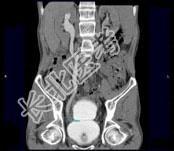

- 多项选择题男,53岁, 无痛性血尿2个月余,CT扫描如图示, 下列说法正确的是 ( )

A、右侧输尿管下段可见沿输尿管走行的软组织肿块影

B、软组织肿块边缘毛糙不平

C、其上方的输尿管扩张

D、考虑为输尿管移行细胞癌

E、考虑为输尿管内血块